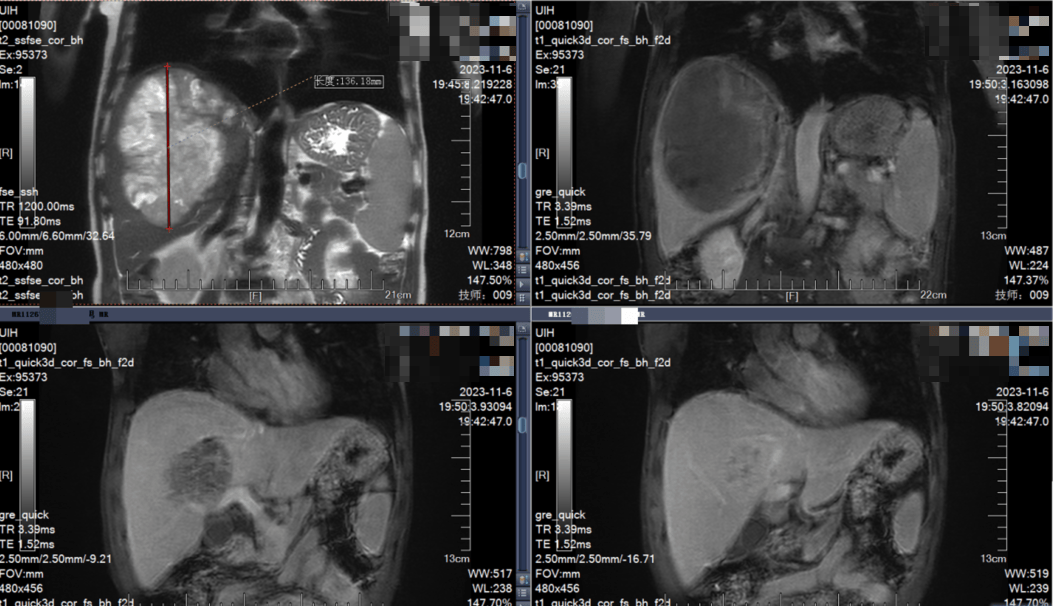

紧接着,第二个周期的治疗在10月展开。2023年11月初的复查结果显示,AFP水平已经降至正常水平(3.5 ng/mL),肿瘤最大径进一步缩小至13.62 cm,达到了影像学上的部分缓解(PR)。最关键的是,原先被肿瘤紧密包裹、模糊不清的第二肝门区变得清晰,肝中静脉根部“重见天日”,门静脉右前支也与肿瘤有了清晰的界限。

2023年11月6日 MRI

经过3D重建技术精确计算,预计切除肿瘤所在的右半肝后,剩余的肝脏体积占标准肝体积的49%,远高于40%的安全底线。当王效谦教授微笑着告诉王先生“我们可以准备手术了”时,希望的光芒彻底驱散了密布的阴霾,王先生和家人几乎雀跃了起来。